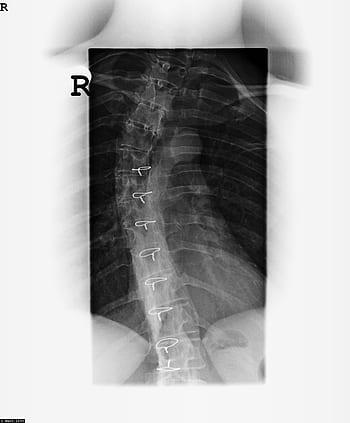

Al igual que una cámara, la película de rayos X se desarrolla según las áreas expuestas a los rayos X. Las áreas blancas muestran los tejidos más densos, como los huesos que han absorbido los rayos X, mientras que las áreas negras en una radiografía representan áreas donde los rayos X han pasado a través de los tejidos blandos.